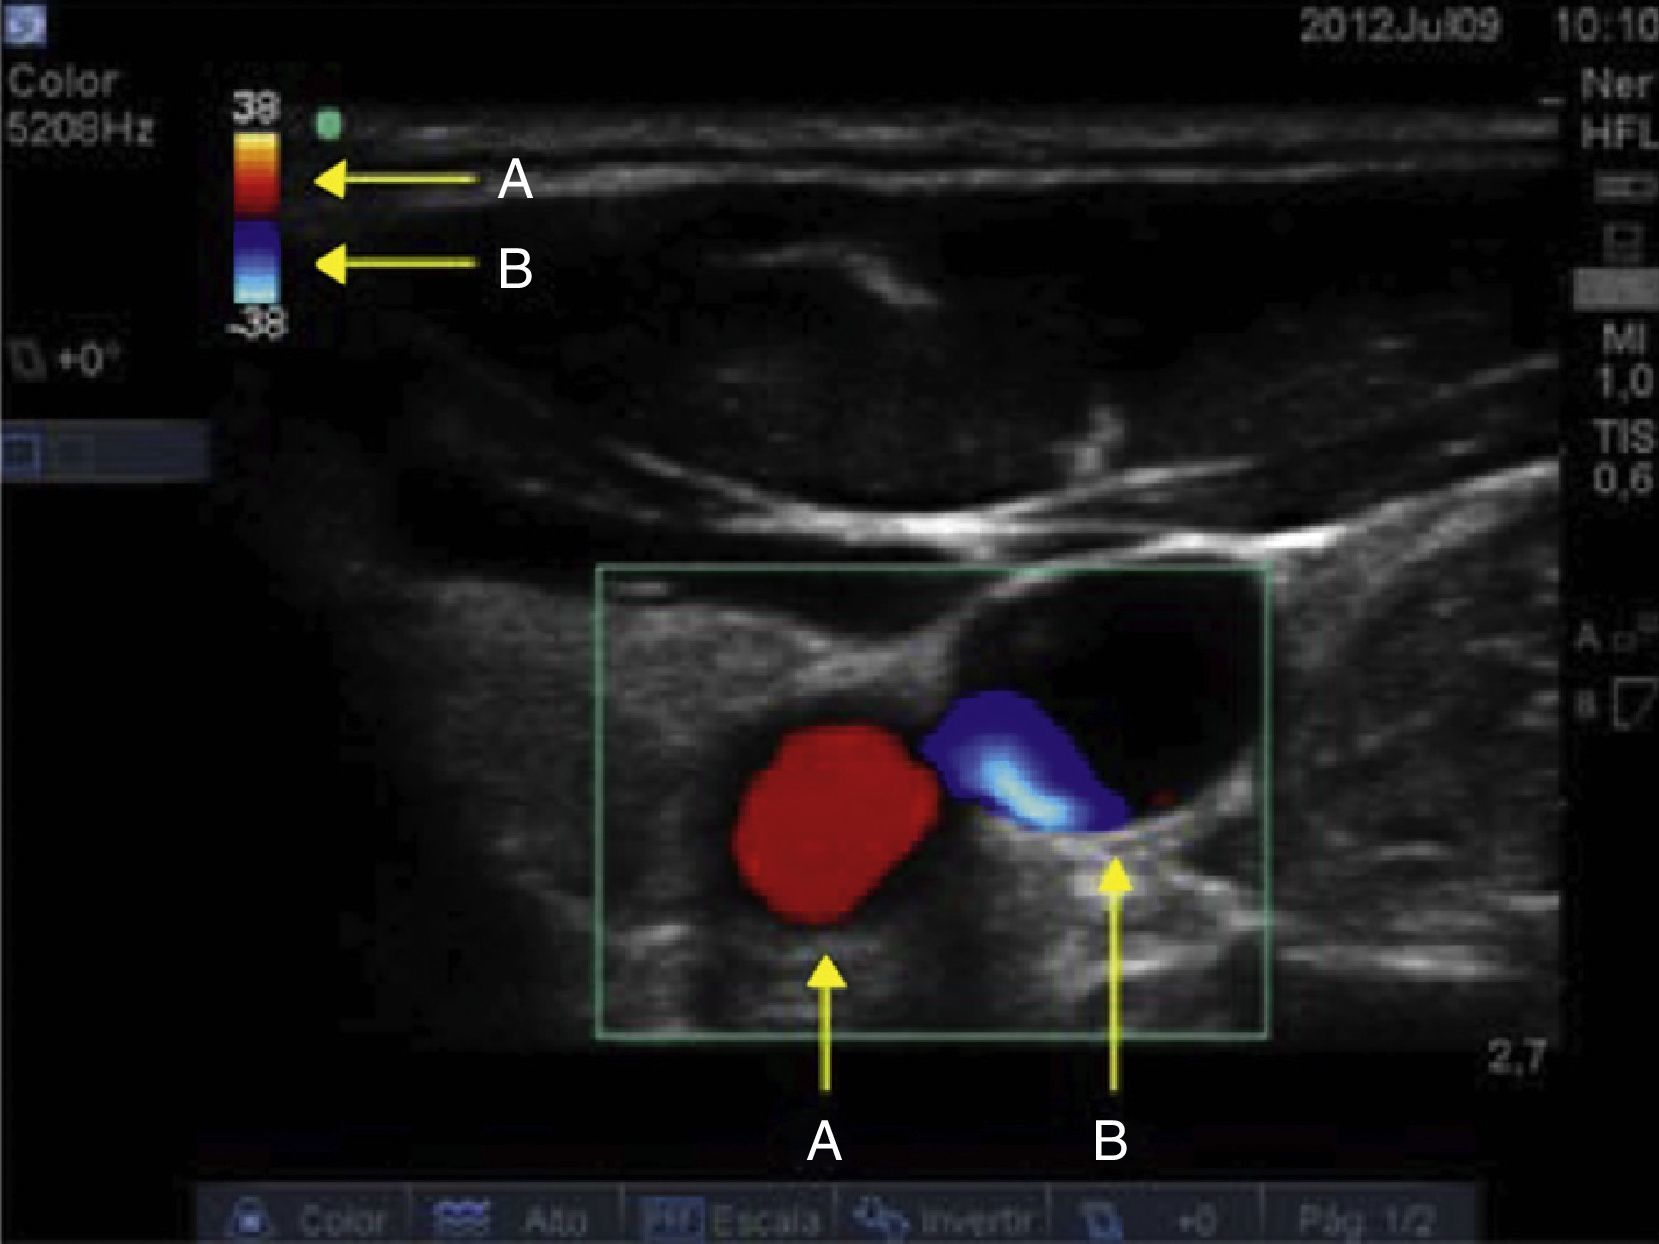

Al determinar la dirección y la velocidad del flujo de la masa globular con la valoración doppler color y doppler pulsado se complementa de forma importante el proceso de identificación vascular venosa y arterial. Teniendo un ángulo de valoración con respecto a la piel entre 30-60 grados y con dirección caudal, se valora el doppler color. La imagen obtenida identificará un flujo en color rojo correspondiente a la sangre que se aproxima al transductor, es decir, el flujo sanguíneo proveniente del corazón. El flujo visualizado en color azul corresponde a la sangre que se aleja del transductor, en este caso el flujo sanguíneo que viene del cerebro y terminará en el corazón (fig. 6).

Valoración ecográfica doppler color con dirección caudal. A)Véase el ángulo de incidencia de 30-60 grados entre el eje del transductor y los vasos del cuello. B)El flujo que se aproxima corresponde al arterial, y su color de visualización es rojo. El flujo en color azul corresponde a la sangre que se dirige al corazón, es decir, el flujo venoso.

Fuente: autores.

En este mismo punto, si cambiamos el ángulo de valoración con dirección cefálica (120-150°) visualizamos un flujo de color rojo, el cual corresponde a la sangre proveniente del cerebro. El flujo en color azul corresponderá a la sangre arterial, que proviene del corazón y llegará hasta el cerebro (fig. 7).

Valoración ecográfica doppler color con dirección cefálica. A)Se cambia el ángulo de incidencia de 120-150 grados entre el eje del transductor y los vasos del cuello. B)En este caso, el flujo que se aproxima corresponde al retorno venoso cerebral, y su color de visualización es rojo. El flujo en color azul corresponde a la sangre que se dirige al cerebro, es decir, el flujo arterial.